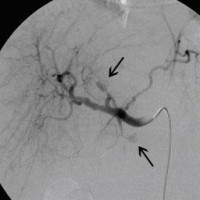

Postoperative abdominelle Blutungen bei chronischer Pankreatitis vor Embolisation der Art. gastroduodenalis mittels Metallspiralen (Coils)

(Bild 2 von 5)